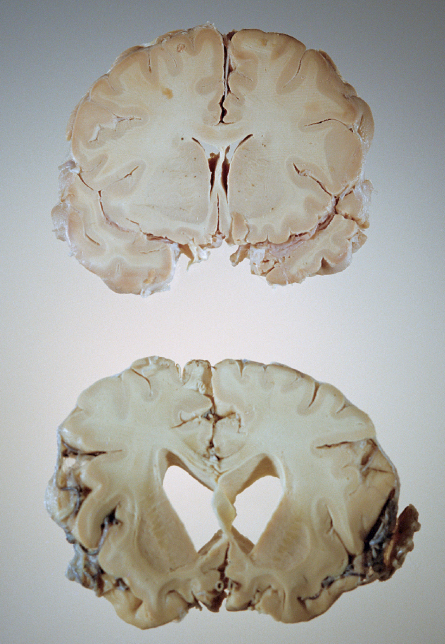

Feature Health & Medicine Memories Can’t Wait Researchers rethink the role of amyloid in causing Alzheimer’s By Laura Sanders February 25, 2011 at 6:00 pm - More than 2 years ago Share this:Share Share via email (Opens in new window) Email Click to share on Facebook (Opens in new window) Facebook Click to share on Reddit (Opens in new window) Reddit Click to share on X (Opens in new window) X Click to print (Opens in new window) Print The polite term for what Alzheimer’s disease does to the brain is “neurodegeneration.” Differences in a healthy brain (top) and a diseased one (bottom) clearly show the damage wrought by Alzheimer’s. © Maggie Steber/National Geographic Society, Corbis ALZHEIMER’S BOOM As the baby boomers age, the number of elderly Americans with Alzheimer’s is projected to reach 13.5